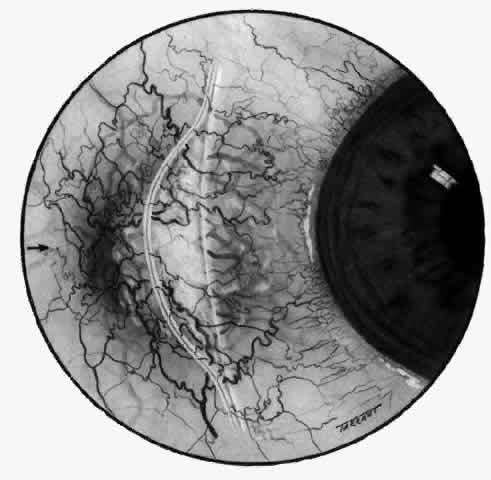

With the increasing use of anterior segment fluorescein angiography in the early detection of severe necrotizing disease of the sclera, it is necessary to have an understanding of the normal anatomy of the vasculature of the anterior segment of the eye.3–5 The blood supply to this region is enormous, being derived from the anterior ciliary arteries, but with extensive collateral arterial anastomoses to the posterior ciliary arteries at the root of the iris (Fig. 1). The anterior system is readily visible with the slit lamp and by anterior segment fluorescein angiography, especially if the eye is inflamed, and its recognition is of vital importance in the differentiation of episcleral and scleral conditions. The separation and displacement of these vascular layers give the most important clinical clues to the site and, hence, the severity of the inflammation. On slit lamp examination, three layers of vessels are readily visible. The conjunctival plexus, which is the most superficial layer of vessels, can be moved over the underlying structures. The superficial episcleral capillary plexus (Fig. 2) is a radially arranged series of vessels lying within the parietal layer of Tenon's capsule. The vessels in this layer anastomose at the limbus with the conjunctival vessels, with other members of the same plexus, and with the deep plexus. The deep episcleral capillary network (see Fig. 2) is closely applied to the sclera in the visceral layer of Tenon's capsule. The vessels anastomose freely with each other, forming a syncytium. The large vessels to and from the intrascleral plexus traverse the episclera near the insertions of the muscles. The conjunctival and superficial episcleral vessels can be blanched with 1:1000 epinephrine or 10% phenylephrine, but the deep vessels are affected slightly. This is of considerable assistance when attempting to differentiate deep and superficial inflammation.

Fig. 1. Anterior view montage of a cynomolgus monkey ocular casting with Tenon's and episcleral vessels removed. The anterior ciliary arteries (ACA) arborize at the limbus and interconnect via their lateral branches to form the episcleral circle. (CM, ciliary muscle capillary bed; CV, choroidal veins; EC, episcleral circle. (Original magnification, X20). (Morrison JC, van Buskirk EM: Anterior collateral circulation in the primate eye. Ophthalmology 90:707, 1983)

Fig. 2. The normal relationships of the capillary networks that can be seen with the slit lamp are a conjunctival (easily mobile) network, a superficial episcleral network in the parietal layer of Tenon's capsule, and a deep episcleral plexus closely applied to the sclera. These relationships are much more obvious in inflamed eyes (see Figs. 13, 14, and 30). (Watson PG, Hayreh S, Awdry P: Episcleritis and scleritis. Br J Ophthalmol 52(3):278– 279, 1968)